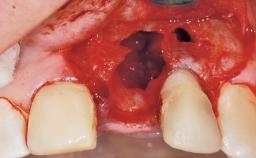

Immediate Flapless Placement of an Implant in a Maxillary Right Lateral Incisor Site

This 43-year-old male patient, a non-smoker, came to our practice because of a fracture of tooth 12 caused by a bicycle accident. Due to the combined para- and infrabony crown and root fracture, tooth extraction, and subsequent implant placement were suggested to the patient as the therapy of choice. The patient had high esthetic expectations with regard to the treatment outcome and asked for an immediate fixed provisional restoration. His individual esthetic risk profile summed up to a medium esthetic risk.

Loading Protocol Immediate

Provisional Implant-Supported Prosthesis Prosthodontic margin > 3 mm apical to mucosal margin Prosthodontic margin > 3 mm apical to mucosal margin